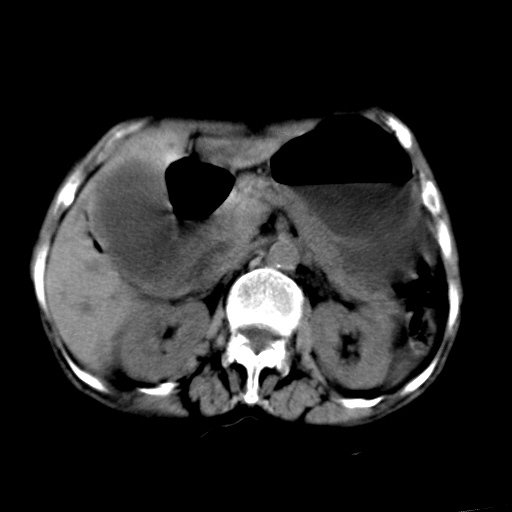

以下是引用杀毒软件在2009-3-4 17:38:00的发言:[br]为何没有喝照影剂呀? 胆总管及肝内胆管扩张,增强吧。[br][br]考虑-----十二指肠占位----建议----十二指肠镜检查[br][br]

以下是引用jiangjing在2009-3-4 17:45:00的发言:[br]低位胆道梗阻。十二指肠降段局部管壁增厚。扫描效果不理想,建议ct增强及ercp。

以下是引用杀毒软件在2009-3-4 17:38:00的发言:[br]为何没有喝照影剂呀? 胆总管及肝内胆管扩张,。增强吧。[br][br]考虑-----十二指肠占位----建议----十二指肠镜检查[br][br][br][br][本贴已被 杀毒软件 于 2009-3-4 17:56:38 修改过]